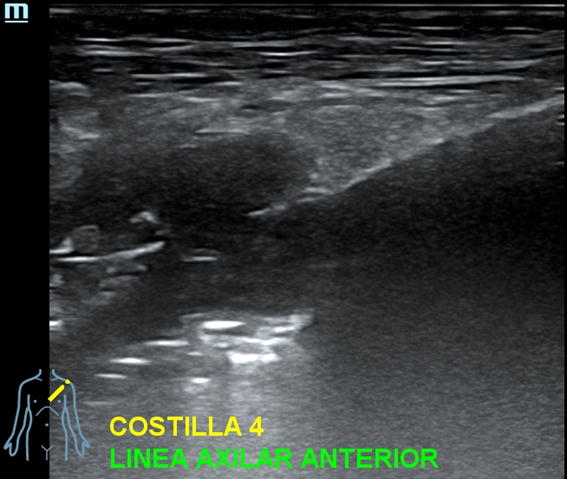

Se decide completar la exploración con ecografía clínica de las costillas afectadas.

Eco clínica costal: en 3ª y 4ª costillas izquierdas, a nivel de línea axilar anterior, se visualiza lesión que rompe y destruye la cortical infiltrando partes blandas. Hipervascularización con Doppler color.